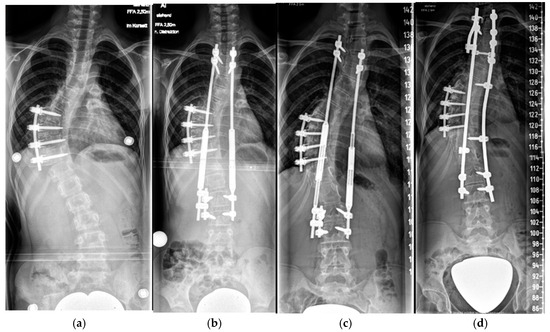

4.2.1. “Early Onset Spinal Deformity”

5.2.1. Growth-Preserving Techniques

| Growth-preserving | 7.7 (±2.3) | 6.7 (±3.6) | 77 (±11.4) | 33.1 (±10.6) | 54.1 (±14.7) | 19.6 (±3) | 22.8 (±2.9) | 0.73 (±0.17) |